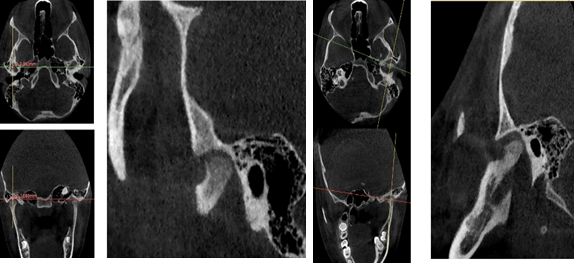

A través de los cortes tomográficos (Figura 3) se pudo observar que la rama mandibular derecha medía 43.85 mm y la izquierda 39.53 mm dando una diferencia de 4.34 mm lo que evidencia que la asimetría que presenta la paciente es a causa de la discrepancia de tamaño de las ramas mandibulares (A).

![]()

Figura 3. Planificación y tratamiento de la displasia discal sin reducción

Elaboración: Los autores.

En el corte a nivel de la articulación temporomandibular izquierda se observó un aplanamiento del cóndilo con áreas de cambios osteoartríticos leves (B); en la articulación temporomandibular derecha el cóndilo se encuentra con una severa osteoartritis que muestra una imagen hipodensa a nivel condilar compatible con un quiste subcondral (C).

Diagnóstico de ATM: La paciente presenta una displasia discal sin reducción bilateral.

Plan de tratamiento: Debido a todo lo expuesto se decidió colocar un aparato de avance mandibular tipo monoblock para recapturar el disco. Para ello se inició con la realización de una mordida constructiva para la confección del aparato, se llevó a una coincidencia de las líneas media y un adelantamiento mandibular de 3 mm (Figuras D, E y F). Posteriormente se envió los registros para la confección del dispositivo de avance mandibular tipo monoblock (Klammt Clase II) que fue instalado en marzo del 2023 constatando de que se encuentre totalmente adaptado (G), las indicaciones de uso fueron más de 20 horas al día aconsejando que la paciente se lo retire únicamente para comer y para el aseo respectivo. Los controles se realizaron a las 2 semanas y después con una frecuencia mensual durante 12 meses.